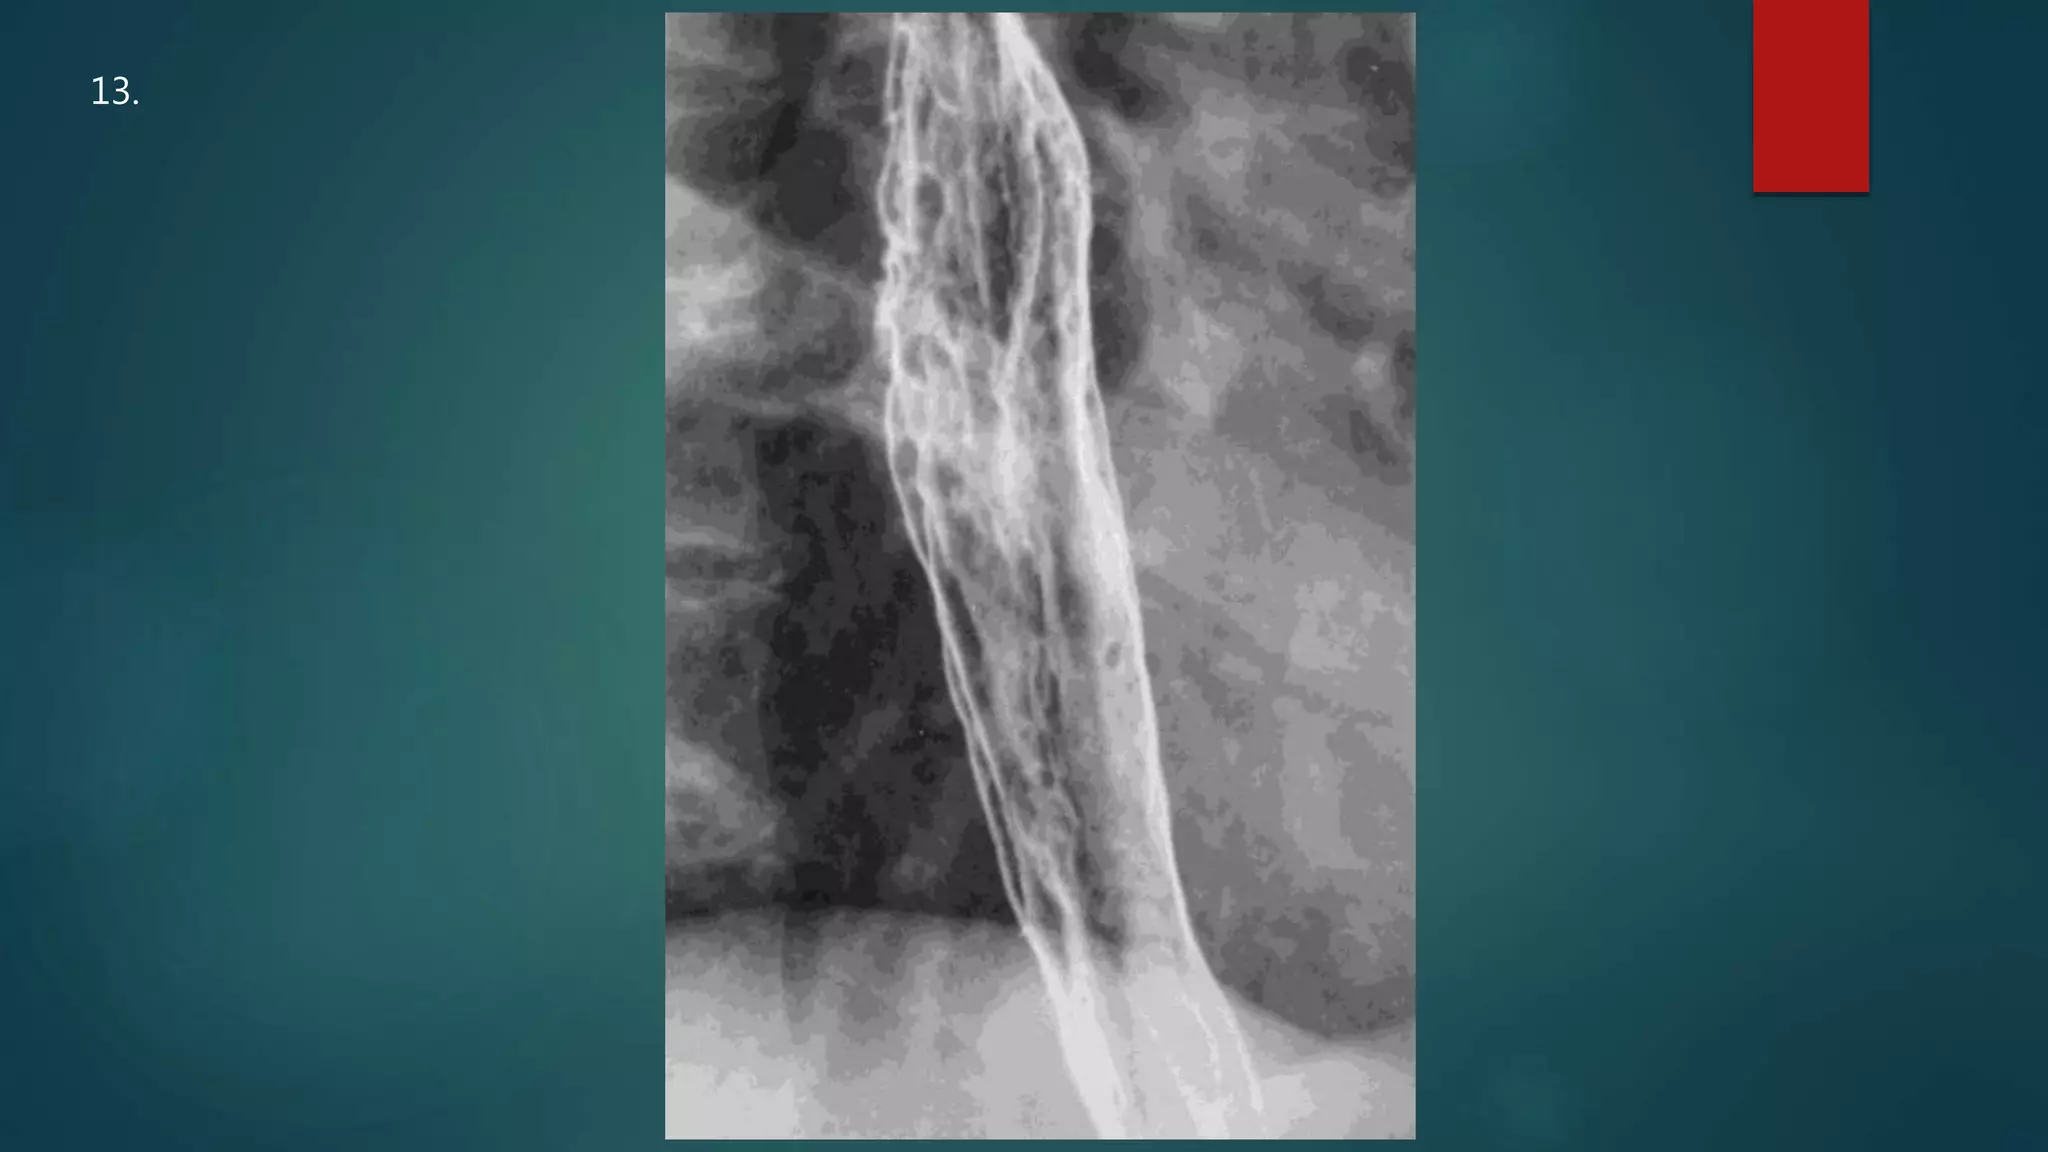

This document appears to be a medical report discussing several patients. It mentions a 35-year-old who was in a severe motor vehicle accident and an 81-year-old with a history of a non-vegetarian diet who had a perforated bowel from a chicken bone. The document provides few other details across its 25 numbered entries and was authored by Dr. Anish Choudhary for junior year 3 on May 30, 2016.